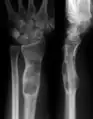

X-ray showing enchondromas localized in the lower part of the radius of a 37-year-old patient affected with Ollier disease